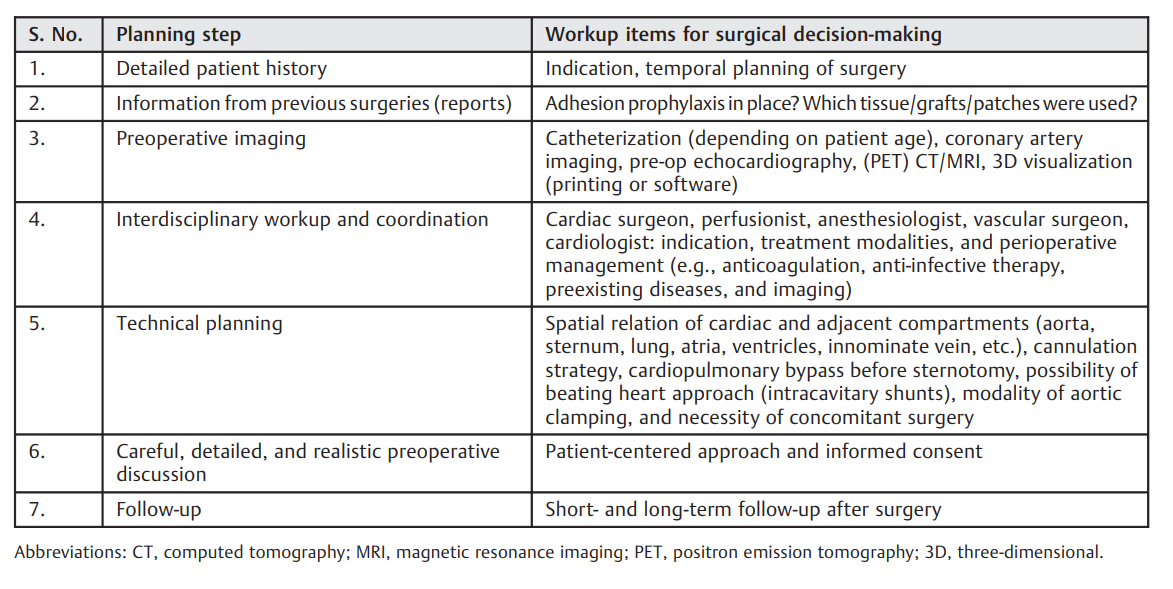

本病例展示了,在第四次心脏重做手术中成功治疗真菌性同种移植物心内膜炎需要经过精心考虑的手术方案。表1的清单可以帮助规划复杂心脏重做手术。在这个特殊案例中描述的所有技术考虑都增强了这个高要求手术的可行性。

表1. 显示复杂心脏重做手术前后七个计划步骤清单的流程图。